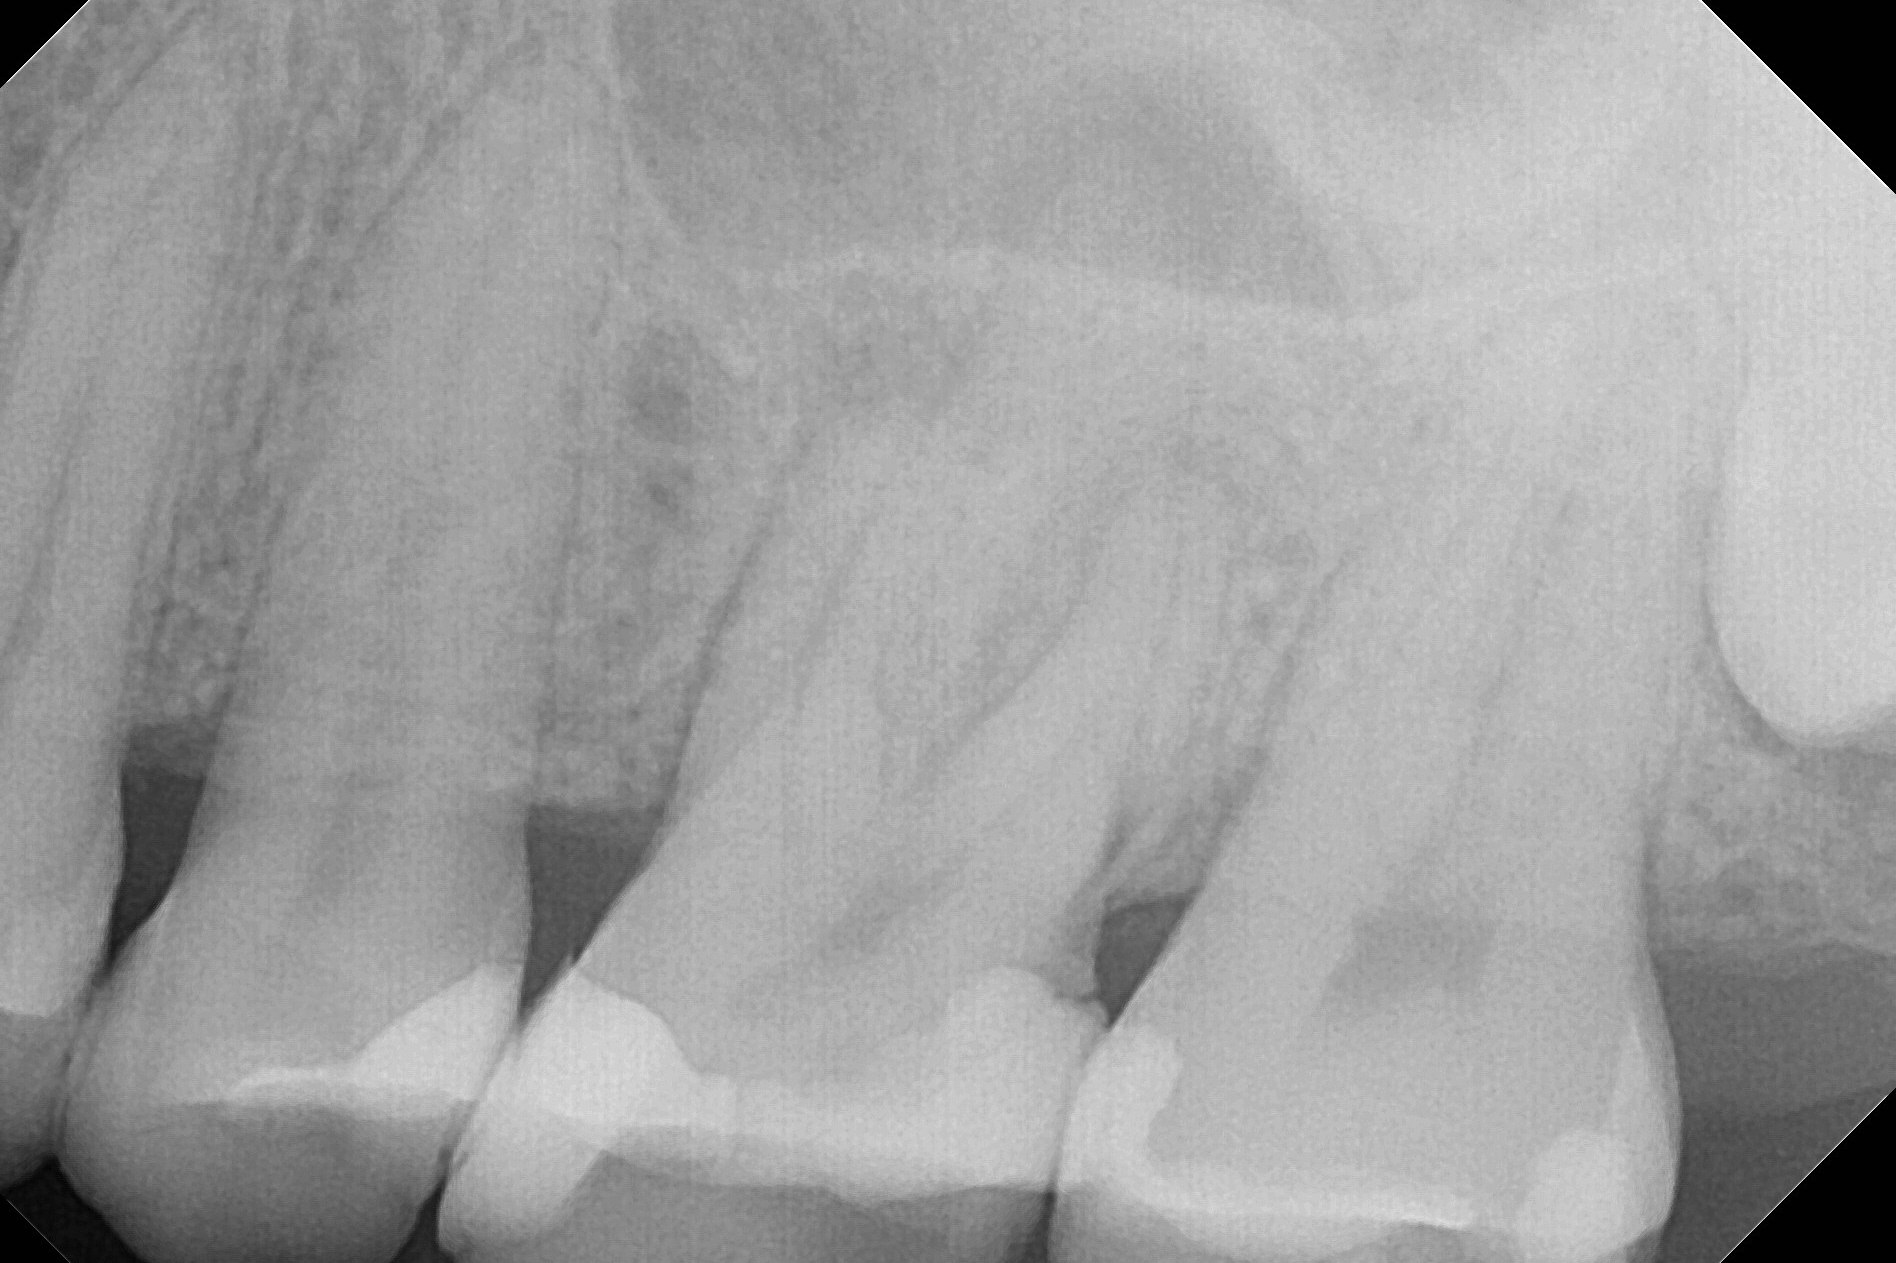

A 55-year-old woman has an implant at #3 (Fig.1). There has been swelling and periapical radiolucency associated with #14 for > 6 months (Fig.2). Finally a mesiodistal crack is found. If infection with bone loss is too severe, socket preservation will be performed. The depth of initial osteotomy in the septum will be 10 mm (Fig.3). Try not to perforate sinus floor. Place an IBS implant as large as possible. If the infection is moderate, use IS one.